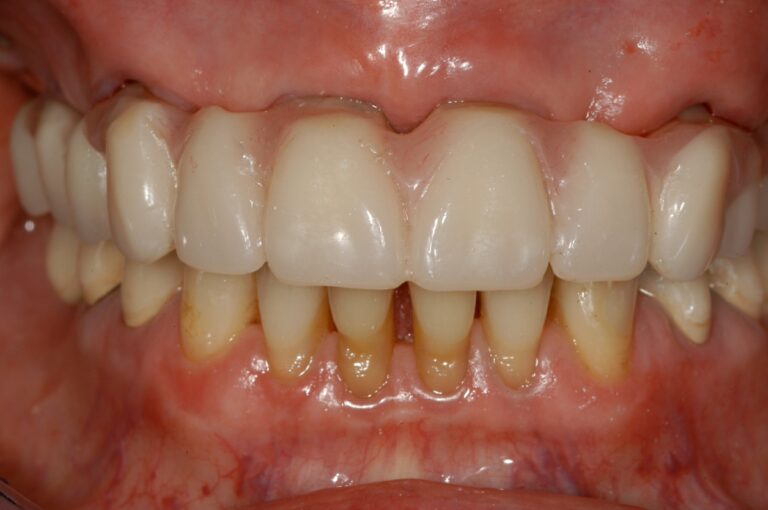

Following improvements to the surfaces of our implants, and utilising experience gained over many years, we can now offer you “FIXED TEETH TODAY”. In most cases, we are able to place a fixed bridge onto the implants immediately after placement. You would therefore arrive at the surgery with loose dentures, and leave with a number of implants placed and a FIXED bridge fitted onto them. This concept reduces the discomfort and healing time following implant placement, and provides immediate satisfaction to our patients. Imagine being able to bite into an apple again for the first time in many years!

The most common cause of partial tooth loss is failing crowns or bridges. The natural roots are then too weak to support a bridge, and have to be extracted. We would usually extract the failing roots, place implants directly into their sockets, and place a fixed bridge immediately afterwards.